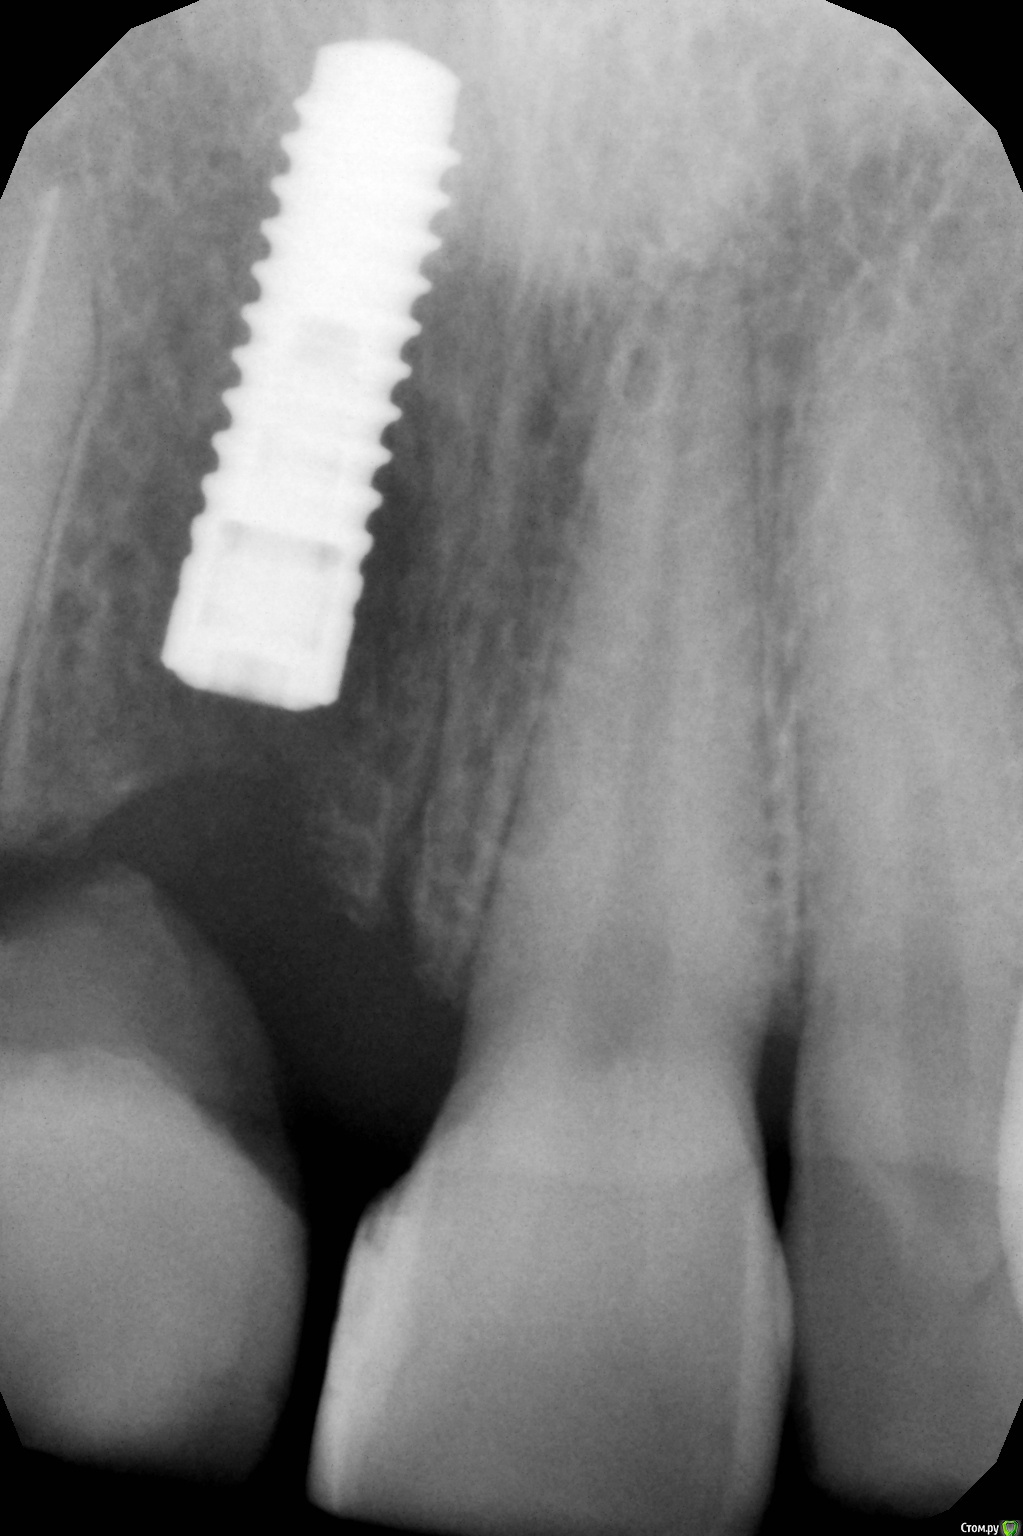

x4ex Опубликовано 16 октября, 2017 Поделиться Опубликовано 16 октября, 2017 (изменено) Три недели назад была имплантация Straumann Bone Level в области 11, вестибулярно подшит сст с бугра, заглушка и ушивание наглухо проленом 5/0. Сверху времянка на 12 с консолью в области 11. На контрольных осмотрах всё ок. Сегодня пришла с пузырём гноя вестибулярно. Со слов появился вчера, болит с позавчерашнего дня. Вскрыл, на коронарных полимпланта грануляции, вестибулярно, медиально и дистально кости нет, нёбно есть и апикально есть. Заглушку выкрутил, имплант не вышел. Выкрутил имплант ключом. В чём может быть причина?P.S. первая имплантация Straumann, абсолютно новым набором, строго по протоколу. Торк был около 30Нсм. Изменено 16 октября, 2017 пользователем x4ex Ссылка на комментарий

x4ex Опубликовано 16 октября, 2017 Автор Поделиться Опубликовано 16 октября, 2017 Графта не было. Насчёт удаления зуба не помню, возможно даже там первичная адентия была.Девушке 27лет и она пришла с коронкой на 12 с консолью на 11. КТ до есть, после только прицельный. Завтра всё добавлю. Имплант ставил субкрестально, примерно на 2мм, исходя из положения зенита соседнего зуба. Ссылка на комментарий

x4ex Опубликовано 17 октября, 2017 Автор Поделиться Опубликовано 17 октября, 2017 Подозрительно не то слово. Клянётся, что проходит каждый год медосмотры и никаких патологий выявлено не было.Не знаю, как изменить шапку, поэтому добавлю снимки сюда. Ссылка на комментарий

Большой Зеленый Опубликовано 17 октября, 2017 Поделиться Опубликовано 17 октября, 2017 Глубоко поставил . Возможно плохо пришил ССТ. Ссылка на комментарий

x4ex Опубликовано 17 октября, 2017 Автор Поделиться Опубликовано 17 октября, 2017 Глубоко поставил . Возможно плохо пришил ССТ.Там от платформы до зенита как раз 3 мм - на последнем снимке виден край времянки. Ну ладно, пусть глубоко, но разве от этого может быть абсцесс? Ссылка на комментарий